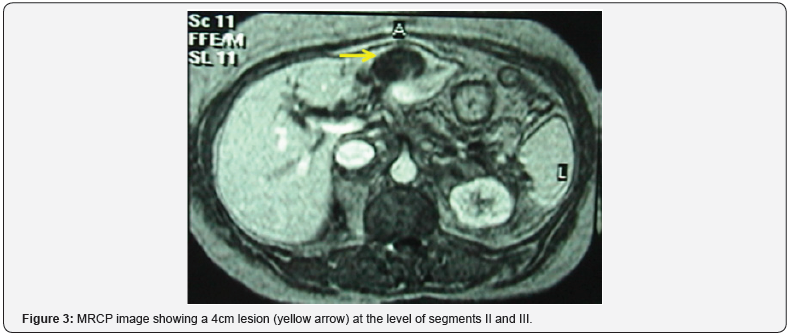

Clinically, she presented with fever (38C), jaundice and tenderness upon palpation of the right upper quadrant. Laboratory exams showed alteration of her liver function tests: bilirubin total / bilirubin direct = 6.6/3.9mg/dl (normal <1.5/<0.5), Gamma GT = 377U/l (normal < 80), Alkaline phosphatase = 271U/l (normal <140). Serologies for hepatitis B and C were negative. Abdominal ultrasound was done and showed a hypoechoic lesion of the left liver measuring at 38mm that correspond to a liver abscess (Figure 1); no dilation of the intra and extra hepatic biliary tree was present. A magnetic resonance cholangiopancreatography (MRCP) revealed an irregular 2cm biliary tree stenosis located at the common hepatic duct and another stenosis located at the left hepatic branch (Figure 2). A circular 4cm lesion was located at the level of segment II and segment III that may correspond to a liver abscess associated with multiple micro abscesses (Figure 3).

a) Type 1 represent a 2-4cm in diameter defect of the extra hepatic biliary tree causing dilation of the intra hepatic tree. Patients whom underwent multiple thrombectomies, exhibit the image of a small infiltrating tumor as well associated to multiple abscesses of the hepatic parenchyma, similar to our case.